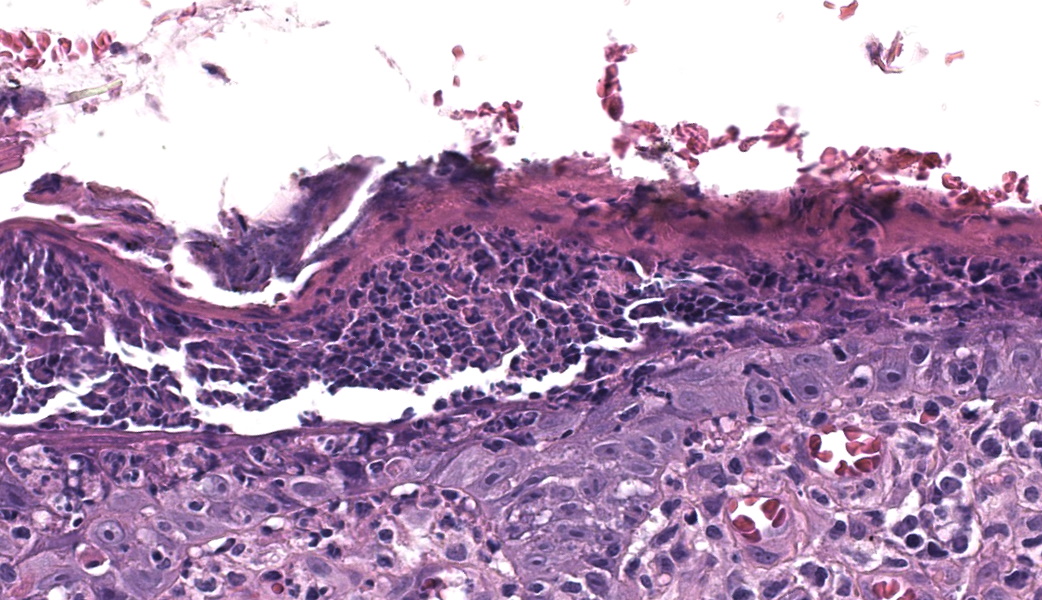

Haired skin. Alle the biopsies are histologically similar. The superficial and mid dermis is obscured by a moderate to severe inflammatory infiltrate, often obscuring the dermo-epidermal junction. The inflammatory infiltrate is represented by a prevalence of lymphocytes and plasma cells, macrophages occasionally engulfing melanin (melanophages), and rare neutrophils. The epidermis is moderately thickened (irregular hyperplasia), with mild intercellular edema (spongiosis) and severe thickening of the stratum corneum by predominantly nucleated (parakeratotic hyperkeratosis) or less frequently non-nucleated keratin (orthokeratotic hyperkeratosis). Numerous apoptotic figures are observed throughout the epidermis, occasionally surrounded by lymphocytic satellitosis. Similar lesions are observed in the hair follicles. There is multifocal erosion or ulceration of the epidermis; the ulcerated areas are obscured by serocellular crusts.Contributor's Morphologic Diagnoses:

Histologically, EM has the features of a cytotoxic (interface) dermatitis. Necrotic keratinocytes are present throughout the epidermis and the adnexal epithelia, often associated with lymphocytic satellitosis. The dermopidermal junction is obscured by lymphocytes and macrophages. Basal keratinocytes could be degenerated.3,5,6 Hyperkeratosis and parakeratosis are commonly seen in canine EM, as opposed to human EM, and may be severe in persistent forms of EM.6 This latter form is called “hyperkeratotic EM”.1

This classic case of erythema multiforme (EM) was much appreciated by participants as it stimulated great discussion on EM and other top differentials, cytotoxic dermatitis pathogenesis, and a handful of “boards-worthy” information. The contributor’s well-written and thorough comment covers much of what was discussed in conference related to the differences between the human and canine manifestations of EM, so focus will be placed on other major discussion points.The major histologic features to help differentiate EM from other conditions are the presence of suprabasilar and transepidermal apoptosis of keratinocytes and satellitosis of lymphocytes around affected keratinocytes.5 Note, however, that if lymphocytes are instead aggregating in and near the epidermis rather than just hovering around affected keratinocytes, epitheliotropic T-cell lymphoma should rise on the differential list. In EM, epithelial dysplasia may also be seen secondary to the concurrent inflammation and necrosis. The same features of transepidermal apoptosis and lymphocyte satellitosis can also be seen in the follicular epithelium, not just in the epidermis! Follicular epithelium may also exhibit hyperpigmentation and vacuolation secondary to inflammation. Parakeratotic hyperkeratosis is often seen in the hyperkeratotic form of EM but is not considered a key diagnostic feature of EM in general.1,5